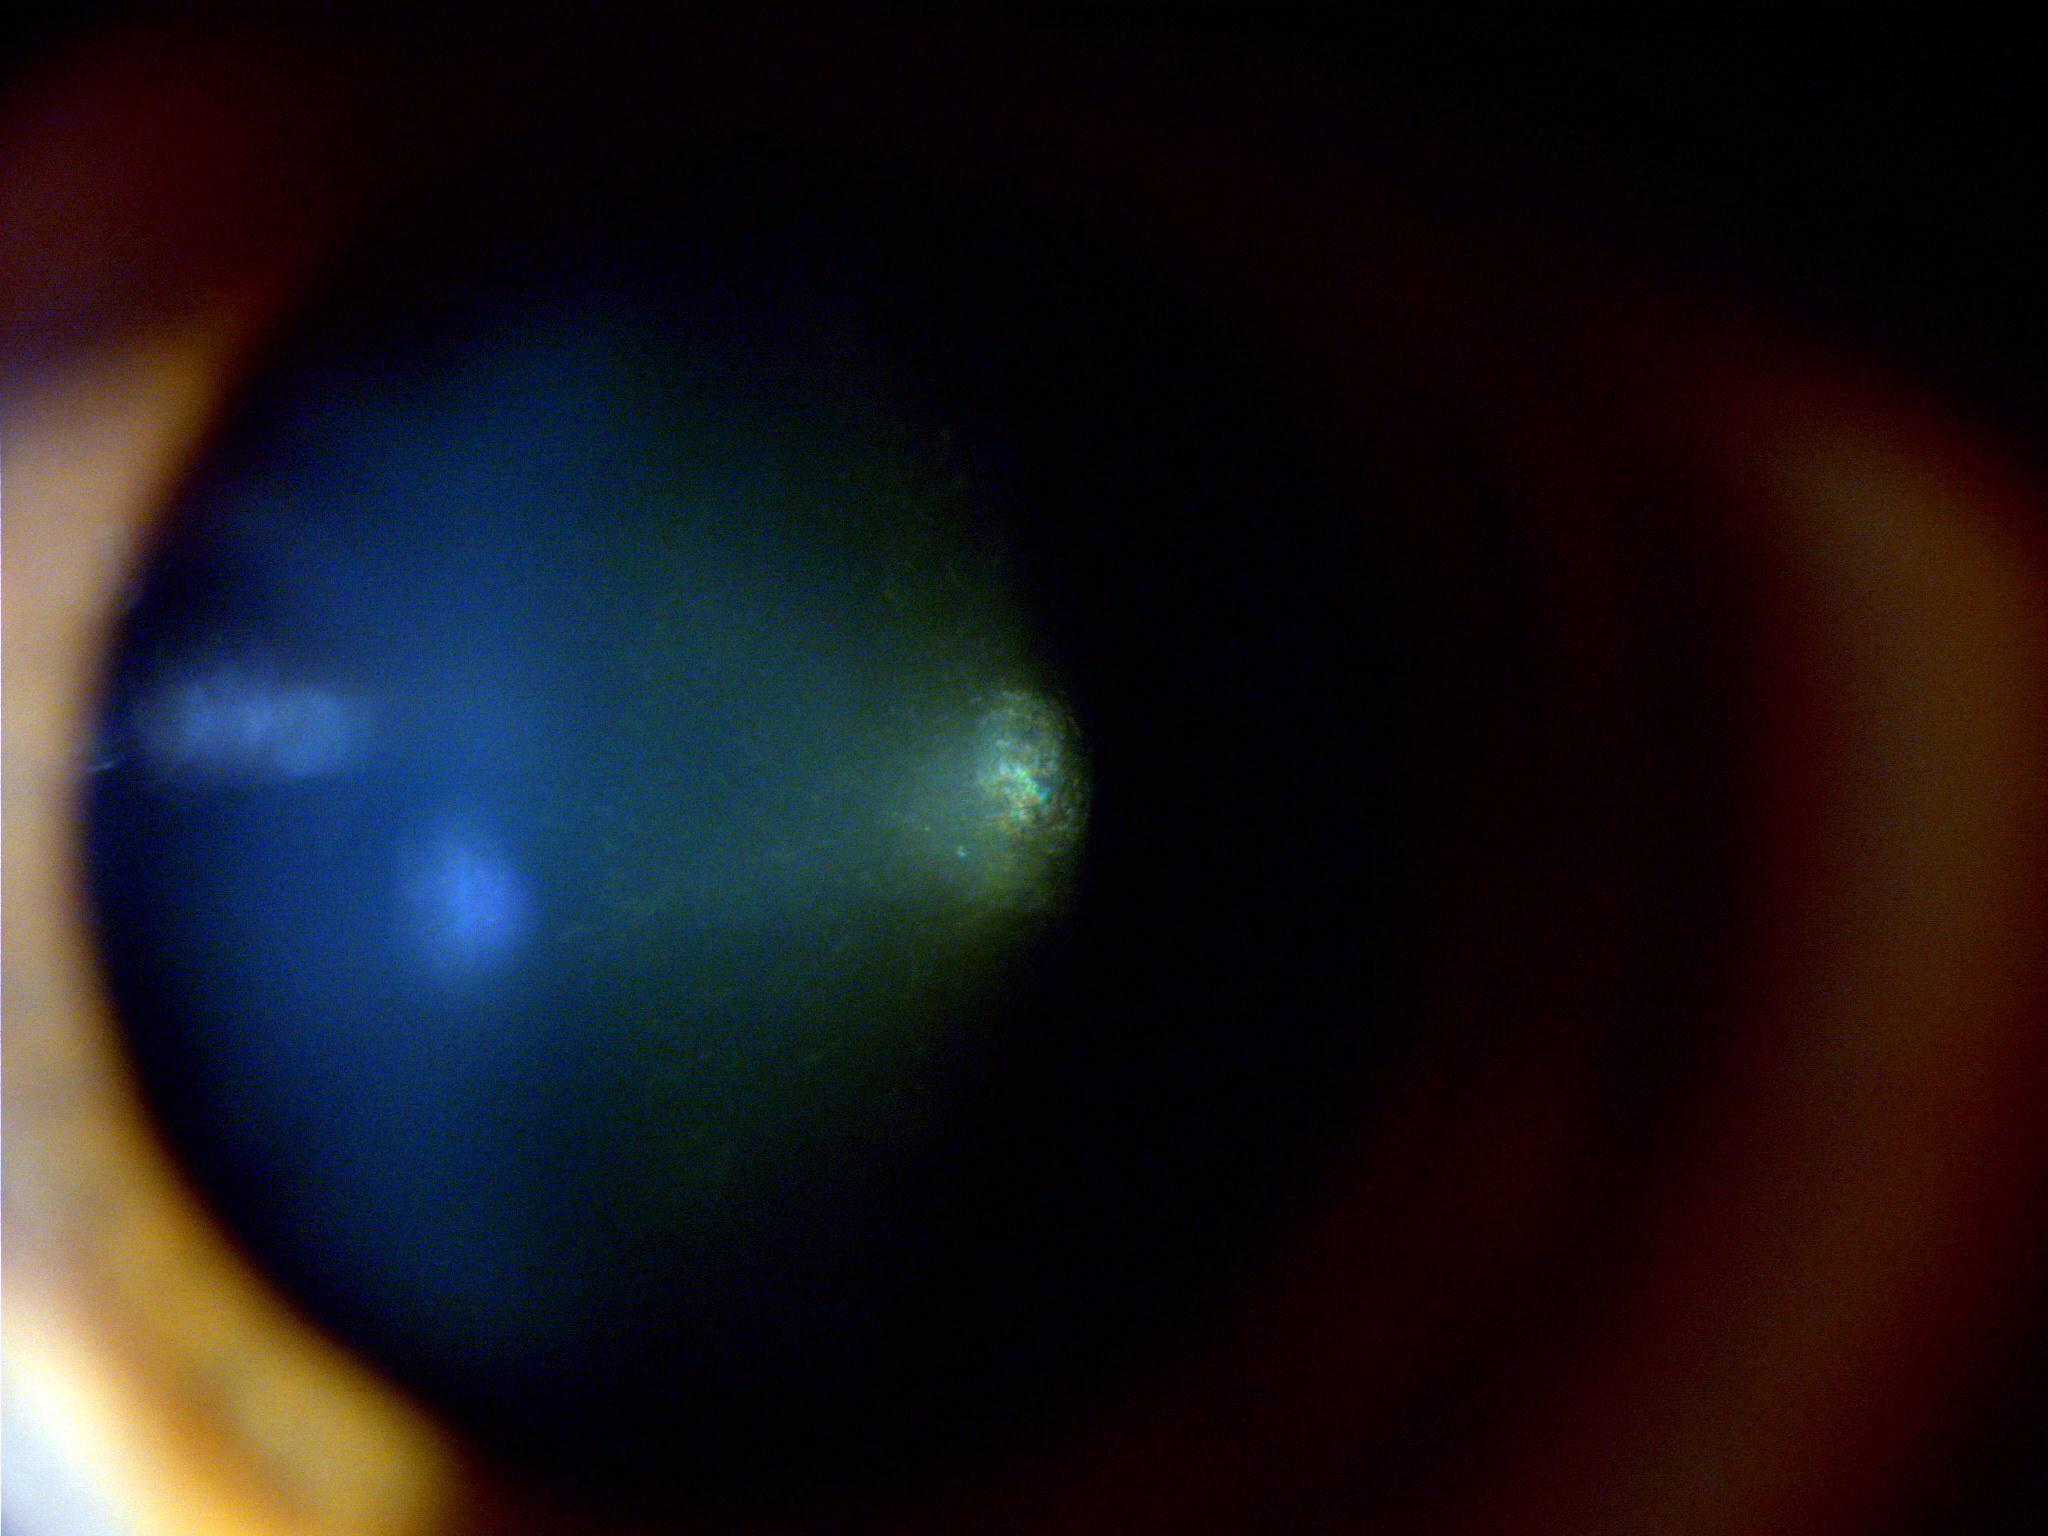

Christmas Tree Cataract Myotonic Dystrophy

CT071620OI Christmas Tree Cataract in Myotonic Dystrophy Myotonic Dystrophy Cataract Type Myotonic dystrophy (dystrophia myotonica), the commonest and most variable of the muscular dystrophies of adult life, has long been. Myotonic dystrophy is the most common inherited muscular dystrophy in adults and presents as two forms, type 1, and type 2. Early onset posterior subscapular cataract (dystrophy</strong>. Myotonic dystrophy type 1 (dm1) is a multisystem disorder that affects skeletal and smooth. Myotonic Dystrophy Cataract Type.